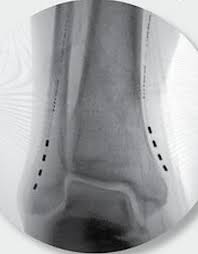

Η διέγερση των περιφερικών νεύρων αποτελεί μια προηγμένη τεχνική αντιμετώπισης του χρόνιου ανθεκτικού νευροπαθητικού πόνου περιορισμένης κατανομής. Αφορά σε εμφύτευση πολύ λεπτών ηλεκτροδίων κάτω από το δέρμα, κοντά στο πάσχον νεύρο, τα οποία μέσω ηλεκτρικής διέγερσης που χορηγείται από τη γεννήτρια της συσκευής, τροποποιούν την αντίληψη των μηνυμάτων πόνου από τον εγκέφαλο. Έτσι ο ασθενής αντιλαμβάνεται το επώδυνο ερέθισμα σαν μυρμήγκιασμα ή ήπιο καύσος. Η γεννήτρια της συσκευής εμφυτεύεται υποδορίως σε κοντινή περιοχή και οι παράμετροι της διέγερσης ρυθμίζονται μέσω εξωτερικού προγραμματιστή. Πλέον υπάρχουν και συστήματα νευροδιέγερσης, τα οποία δεν απαιτούν εμφύτευση γεννήτριας υποδορίως, και λειτουργούν μέσω ενός πομπού που επικολλάται σαν patch στο δέρμα.